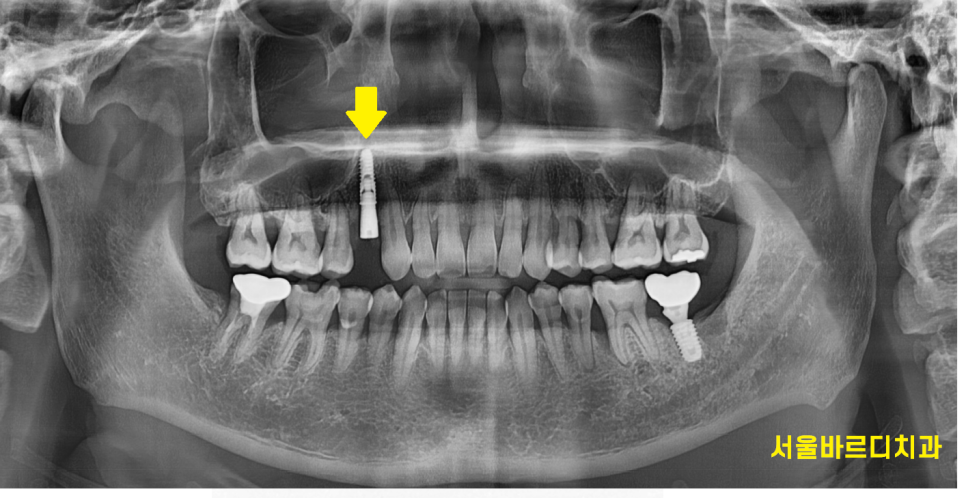

CT 상에서도 뼈가 녹아 치아가 붕~ 떠있는 것을 볼 수 있고요

이럴 때는 발치 후 염증을 깨끗하게 제거

제 2의 치아인 임플란트 식립을 해줍니다.

상일동역 치과에서 임플란트 식립한 사진입니다.

기능을 상실한 치아를 대신하여

임플란트를 심어드렸는데

임플란트 역시 잇몸 뼈에 식립하기에

관리를 해주어야합니다.